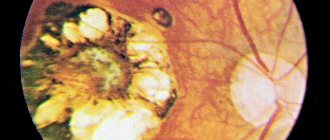

Кровоизлияние в сетчатку

Кровоизлияния в сетчатку чаще относятся к сосудистым заболеваниям и приводят к понижению остроты зрения, отслойке сетчатки, вторичной глаукоме, дистрофии сетчатки и другим заболеваниям.

Причины кровоизлияния в сетчатку могут быть связаны с уплотнением сосудов в пожилом возрасте, вследствие тромбоза (закупорки) центральной вены сетчатки или одной из ее ветвей. Также кровоизлияние в сетчатку может быть вызвано сахарным диабетом, пороками сердца, болезнями крови, ожогами кожи, ушибами и т.д.